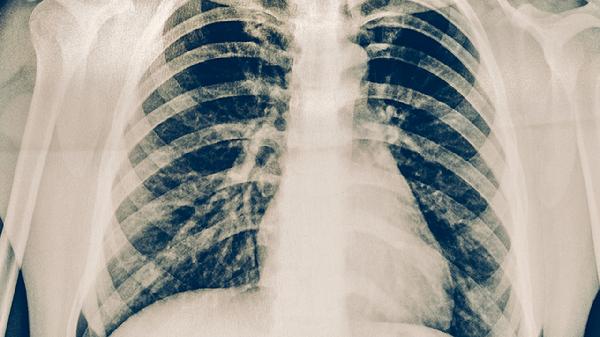

肺結(jié)核患者可通過高蛋白飲食、高維生素飲食、適量碳水化合物、充足水分?jǐn)z入、避免刺激性食物等方式進(jìn)行飲食調(diào)理。肺結(jié)核是由結(jié)核分枝桿菌感染引起的慢性傳染病,合理飲食有助于增強(qiáng)免疫力并輔助治療。